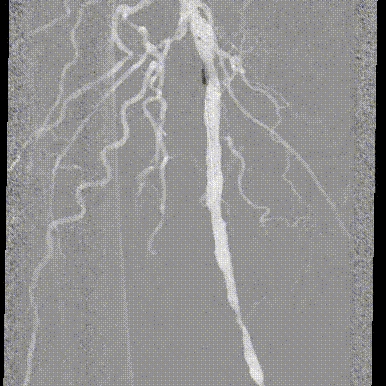

步进造影:股浅动脉起始重度狭窄、中段重度狭窄,腘动脉远端重度狭窄、胫前动脉、胫后动脉闭塞

V-18导丝配合多功能导管通过股浅动脉、腘动狭窄闭塞段,交换0.14导丝远端置于腓动脉中段

步进造影配合血管腔内超声诊断导管提示:股浅动脉全程、腘动脉、胫腓干动脉血流通畅,未见明显夹层、造影剂外溢,远端未见栓塞,膝下动脉如前。